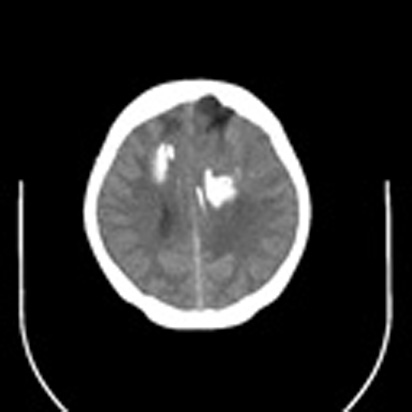

标题: CT16829:女,36,近20天偶有口眼歪斜短暂发作史,近日头痛。

近20天偶有口眼歪斜短暂发作史,近日头痛。患者先做ct发现病变后又做了mri检查,前日上传2次ct图像均未成功,今日补上。

大脑中线部位肿瘤向两侧生长,可见明显钙化影,考虑少枝胶质瘤,建议增强除外脑膜瘤

左额混杂密度肿块,经胼胝体跨越中线向右额叶生长,多考虑少支胶质细胞瘤,建议mr增强扫描,待排除血管畸形。